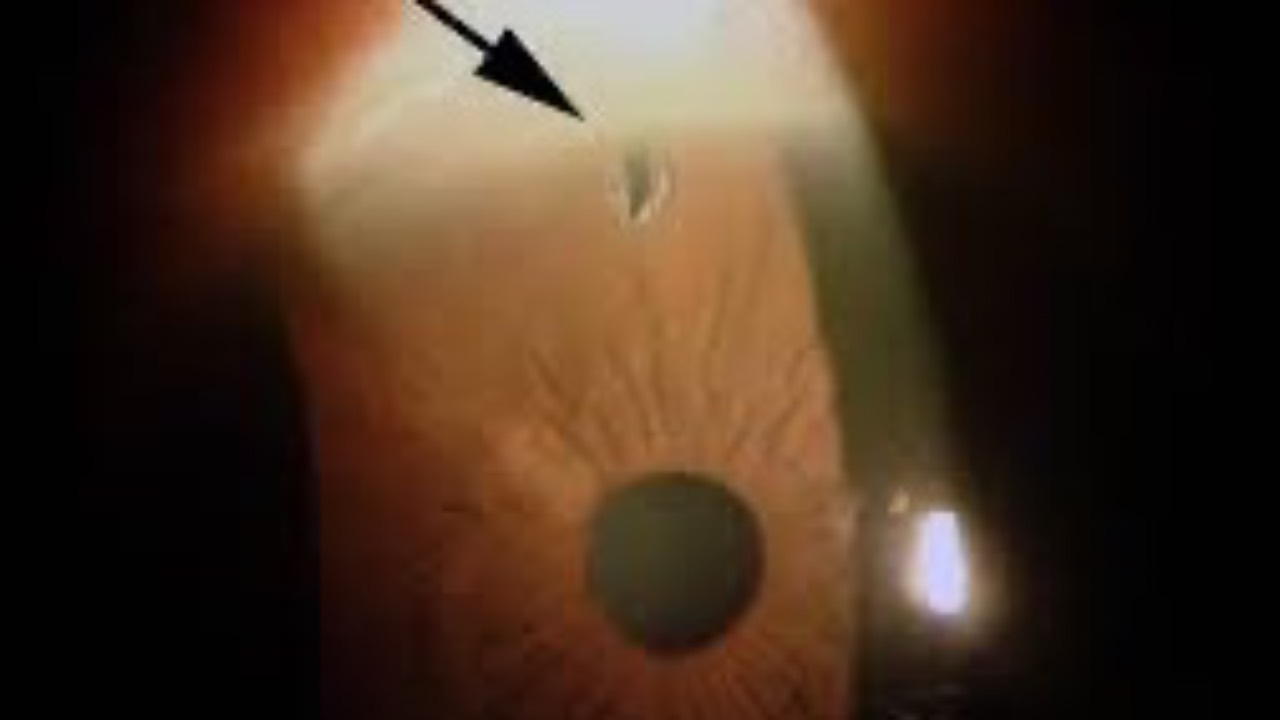

Peripheral Iridotomy (LPI)...should you or shouldn't you?

A systematic review and meta-analysis just published looked at the progression of primary angle closure suspects (PACS) to more advanced stages of angle closure.

The results from 1,997 PACS patients with an average follow-up of 6.2 years,...